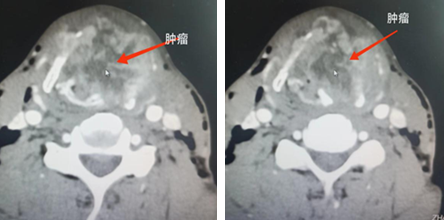

经过近两个月的治疗,放化疗期间患者未出现体重减轻,各项营养指标评价改善,无气管切开的感染、出血等并发症。复查CT,影像学评价肿瘤近完全缓解,喉腔形态基本恢复正常,患者恢复正常呼吸并能言语交流。每次查房时,张先生总是由衷地对医护人员竖起大拇指称赞和感谢。